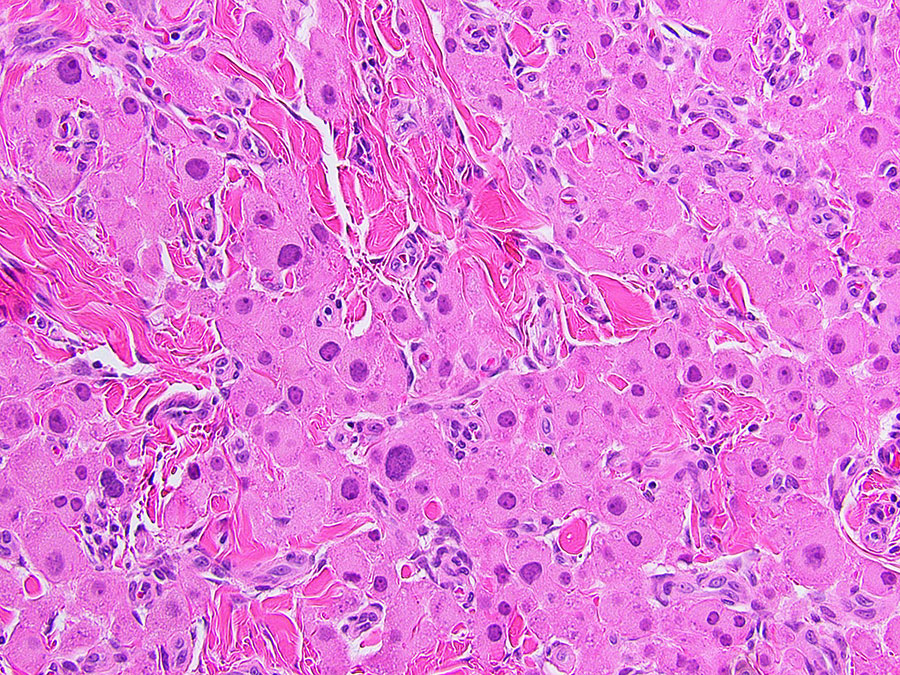

At surgery, there were multiple hard testicular masses with compression of adjacent testicular tissue and dilatation of upstream seminiferous tubules. Microscopic examination of the excised masses showed sheets, cords, and lobules of large, polygonal cells with abundant, finely granular eosinophilic cytoplasm and large pleomorphic nuclei (Figures 1-4). Intracytoplasmic lipochrome pigment was seen in areas (Figure 5). The lesional cells were positive for inhibin (Figure 6), synaptophysin (Figure 7), and CD56 (Figure 8) but negative for androgen receptor (not shown). Adjacent uninvolved testis was unremarkable and showed preserved spermatogenesis.